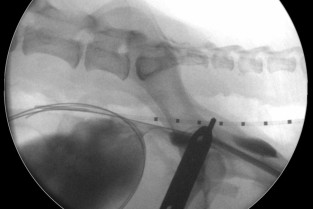

Le Groupe d'Étude en Chirurgie est heureux d’organiser sa 9è journée spécialisée sur le thème de la radiologie interventionnelle, le 29 janvier 2026. Cette journée annuelle de formation vise un public de vétérinaires ayant un fort intérêt pour la chirurgie des tissus et la chirurgie mini-invasive. Elle se tiendra au siège de l'AFVAC Paris 8è.

L’objectif de cette journée est d’élargir son champ de connaissances relatives à la chirurgie interventionnelle des carnivores domestiques, permettant de présenter les principales indications, le matériel indispensable et le déroulement des principales procédures. Le format de cette journée vise à favoriser les échanges avec les conférenciers et entre les participants, permettant à chacun de partager son expérience et ses difficultés.

- Connaître les principales indications de radiologie interventionnelle.

- Identifier le matériel nécessaire à chaque procédure.

- Connaître le principe du déroulement de chacune des procédures.